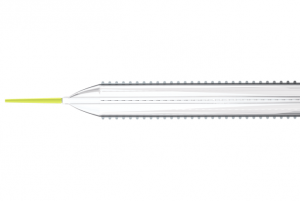

Cagent Vascular announced the results of its PRELUDE-BTK study at LINC 2021 (25–29 January, online). The PRELUDE-BTK study was a prospective, single-arm, multicentre feasibility study to show the safety and efficacy of serration angioplasty.